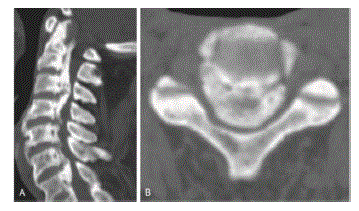

Que achado radiográfico pode ser identificado na tomografia abaixo (Figura 2)?